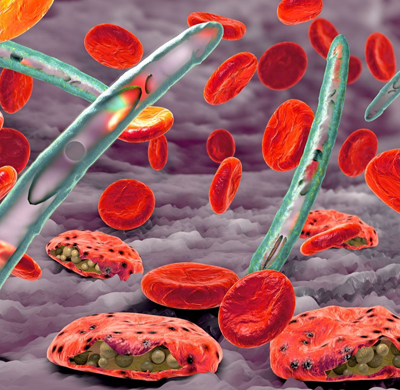

She has brought together a dynamic group of highly skilled professionals, each an expert in their field. Our talented 3D animators combine technical precision with artistic creativity, crafting lifelike, interactive visuals that simplify even the most complex medical concepts. Our production team transforms ideas into captivating cinematic narratives, ensuring each project resonates deeply with its audience. Patient storytellers and communication specialists capture the human essence of healthcare breakthroughs through heartfelt testimonials and insightful KOL interviews that inspire trust and connection.